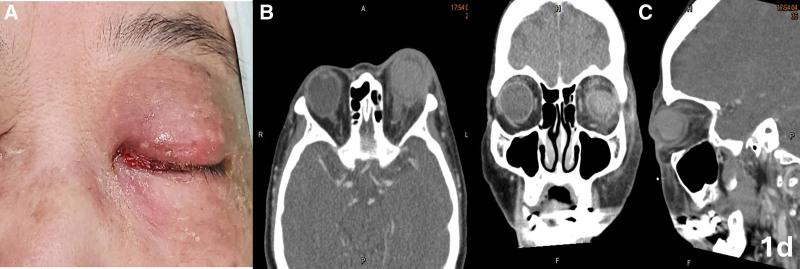

This study reported a case of 71-year-old female with swelling of her left eye 1 week after pars plana vitrectomy and SO tamponade.

Acute infectious endophthalmitis complicated with orbital cellulitis and compartment syndrome in a postvitrectomy SO-filled eye.

The severe inflammatory condition of soft tissue with compartment syndrome and elevated intraocular pressure which could not be controlled ameliorated markedly after initiation of HBOT.